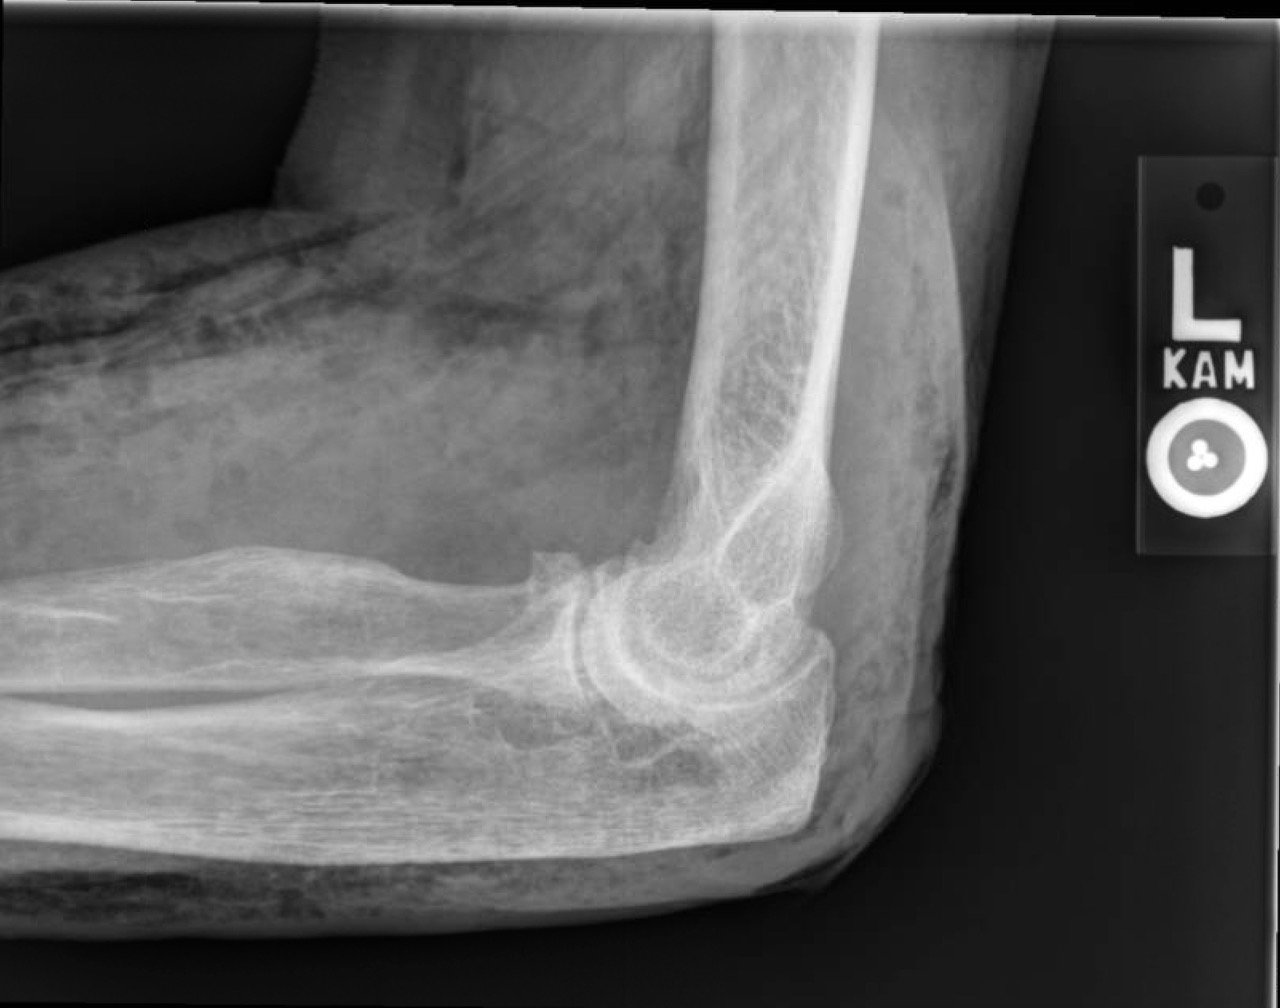

X-Rays of the elbow revealed diffuse striated lucencies throughout the soft tissue, consistent with extensive subcutaneous air throughout the superficial and deep tissues. There was no evidence of a fracture.